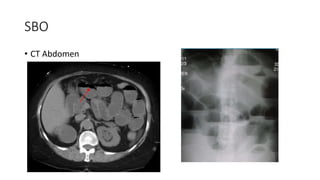

SBO

• CT Abdomen